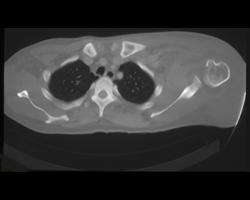

Diagnosis

Stress Fracture Sacrum